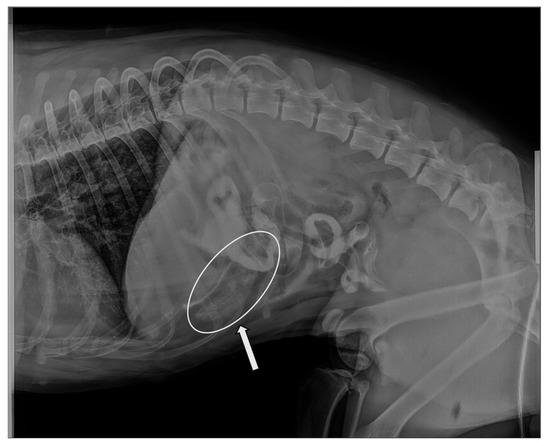

Gastrointestinal Phytobezoars in Small Animals: A Retrospective Study of 18 Cases

A phytobezoar is a compact mass formed by the accumulation of indigestible food fibers (such as cellulose and lignin) within the stomach and/or intestine. To date, only limited reports describe the clinical management and diagnostic approach to gastrointestinal phytobezoars (GIPs) in dogs and [...] Read more.

A phytobezoar is a compact mass formed by the accumulation of indigestible food fibers (such as cellulose and lignin) within the stomach and/or intestine. To date, only limited reports describe the clinical management and diagnostic approach to gastrointestinal phytobezoars (GIPs) in dogs and cats. The aim of this study was to describe the clinical features and diagnostic findings obtained through imaging and instrumental investigations in canine and feline cases with GIPs. Medical records of 25 animals diagnosed with GIPs were reviewed, and data on signalment, clinical signs, imaging findings, and follow-up were collected. Seven animals were excluded because the foreign body (FB) consisted of plastic mixed with fibrous material. Eighteen animals (17 dogs and 1 cat) were included: 8 (44.4%) with gastric involvement, 8 (44.4%) with intestinal localization and 2 (11.1%) with both gastric and intestinal localization. The GIP was removed endoscopically in 3 (16.7%) cases, surgically in 7 (38.9%) cases, extracted from the rectal ampulla in 2 (11.1%) cases, and expelled spontaneously through defecation in 6 (33.3%) cases. GIPs are frequently underdiagnosed, as they are associated with nonspecific gastrointestinal signs. Radiography and ultrasonography offer limited diagnostic value, generally suggesting the presence of an FB without definitively confirming it to be GIP. This study contributes to the current literature by detailing the clinical, diagnostic, and interventional features of GIPs in small animals, representing the first report of this condition in veterinary medicine. Full article

(This article belongs to the Section Companion Animals)

Show Figures

Figure 1